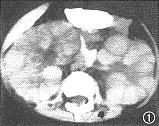

11例白血病肾浸润患儿中,9例为双肾浸润,其中双肾弥漫浸润4例,双肾多发结节浸润5例,9例中ALL 8例,ANLL 1例。CT平扫见弥漫浸润为两肾轮廓增大,肾包膜完整光滑,肾实质明显增厚,肾实质密度无异常,肾窦形态基本正常,增强后肾盂、肾盏显影轻度延迟。B超显示肾影增大、肾实质增厚的同时还显示回声均匀增强。 多发结节浸润的平扫CT见肾实质内多发的略高密度结节影,结节间可见线状低密度影将其分开(图1),结节突起使肾表面呈轻度分叶状。增强后肾实质内结节呈轻微强化,较平扫增长18 HU,密度均匀,结节内无低密度坏死区或出血,结节间见强化后受结节挤压变形的肾实质与集合系统,呈高密度分支状影(图2),肾实质强化程度较正常减低,在结节间自肾被膜下延伸至肾窦,肾盏变形拉长,肾盂显影明显延迟。B超显示肾实质回声增强,内见多发大小不等的结节(图3),中等强度回声,肾结构不清。化疗后复查,CT平扫显示双肾大小、形态基本恢复正常。本组2例呈单发结节浸润,均为ANLL。平扫CT见肾实质局限增厚,表面隆起,密度较正常肾实质略高,境界模糊(图4),增强后见肾实质内单发结节状影轻微强化,较平扫增长22HU,结节与正常肾实质间界限清楚(图5),肾被膜完整。B超显示肾实质内孤立中等强度回声结节(图6),肾结构受挤压变形。化疗后复查B超显示肾形态基本恢复正常。 本组化疗后5例复查CT与B超,显示肾轮廓明显缩小,肾实质厚度、密度或回声接近正常。11例患儿肝、脾均有不同程度增大。8例ALL患儿CT或B超检查同时显示胸腺浸润1例;肺及胸膜浸润4例;肾上腺浸润2例;腹膜后淋巴结浸润1例。3例ANLL患儿除肝、脾增大外CT或B超检查未显示其他脏器浸润。

图1 男,3岁。急性淋巴细胞白血病。双肾多发结节浸润。CT平扫显示两肾轮廓增大,肾实质内多发略高密度结节,结节间线状低密度影